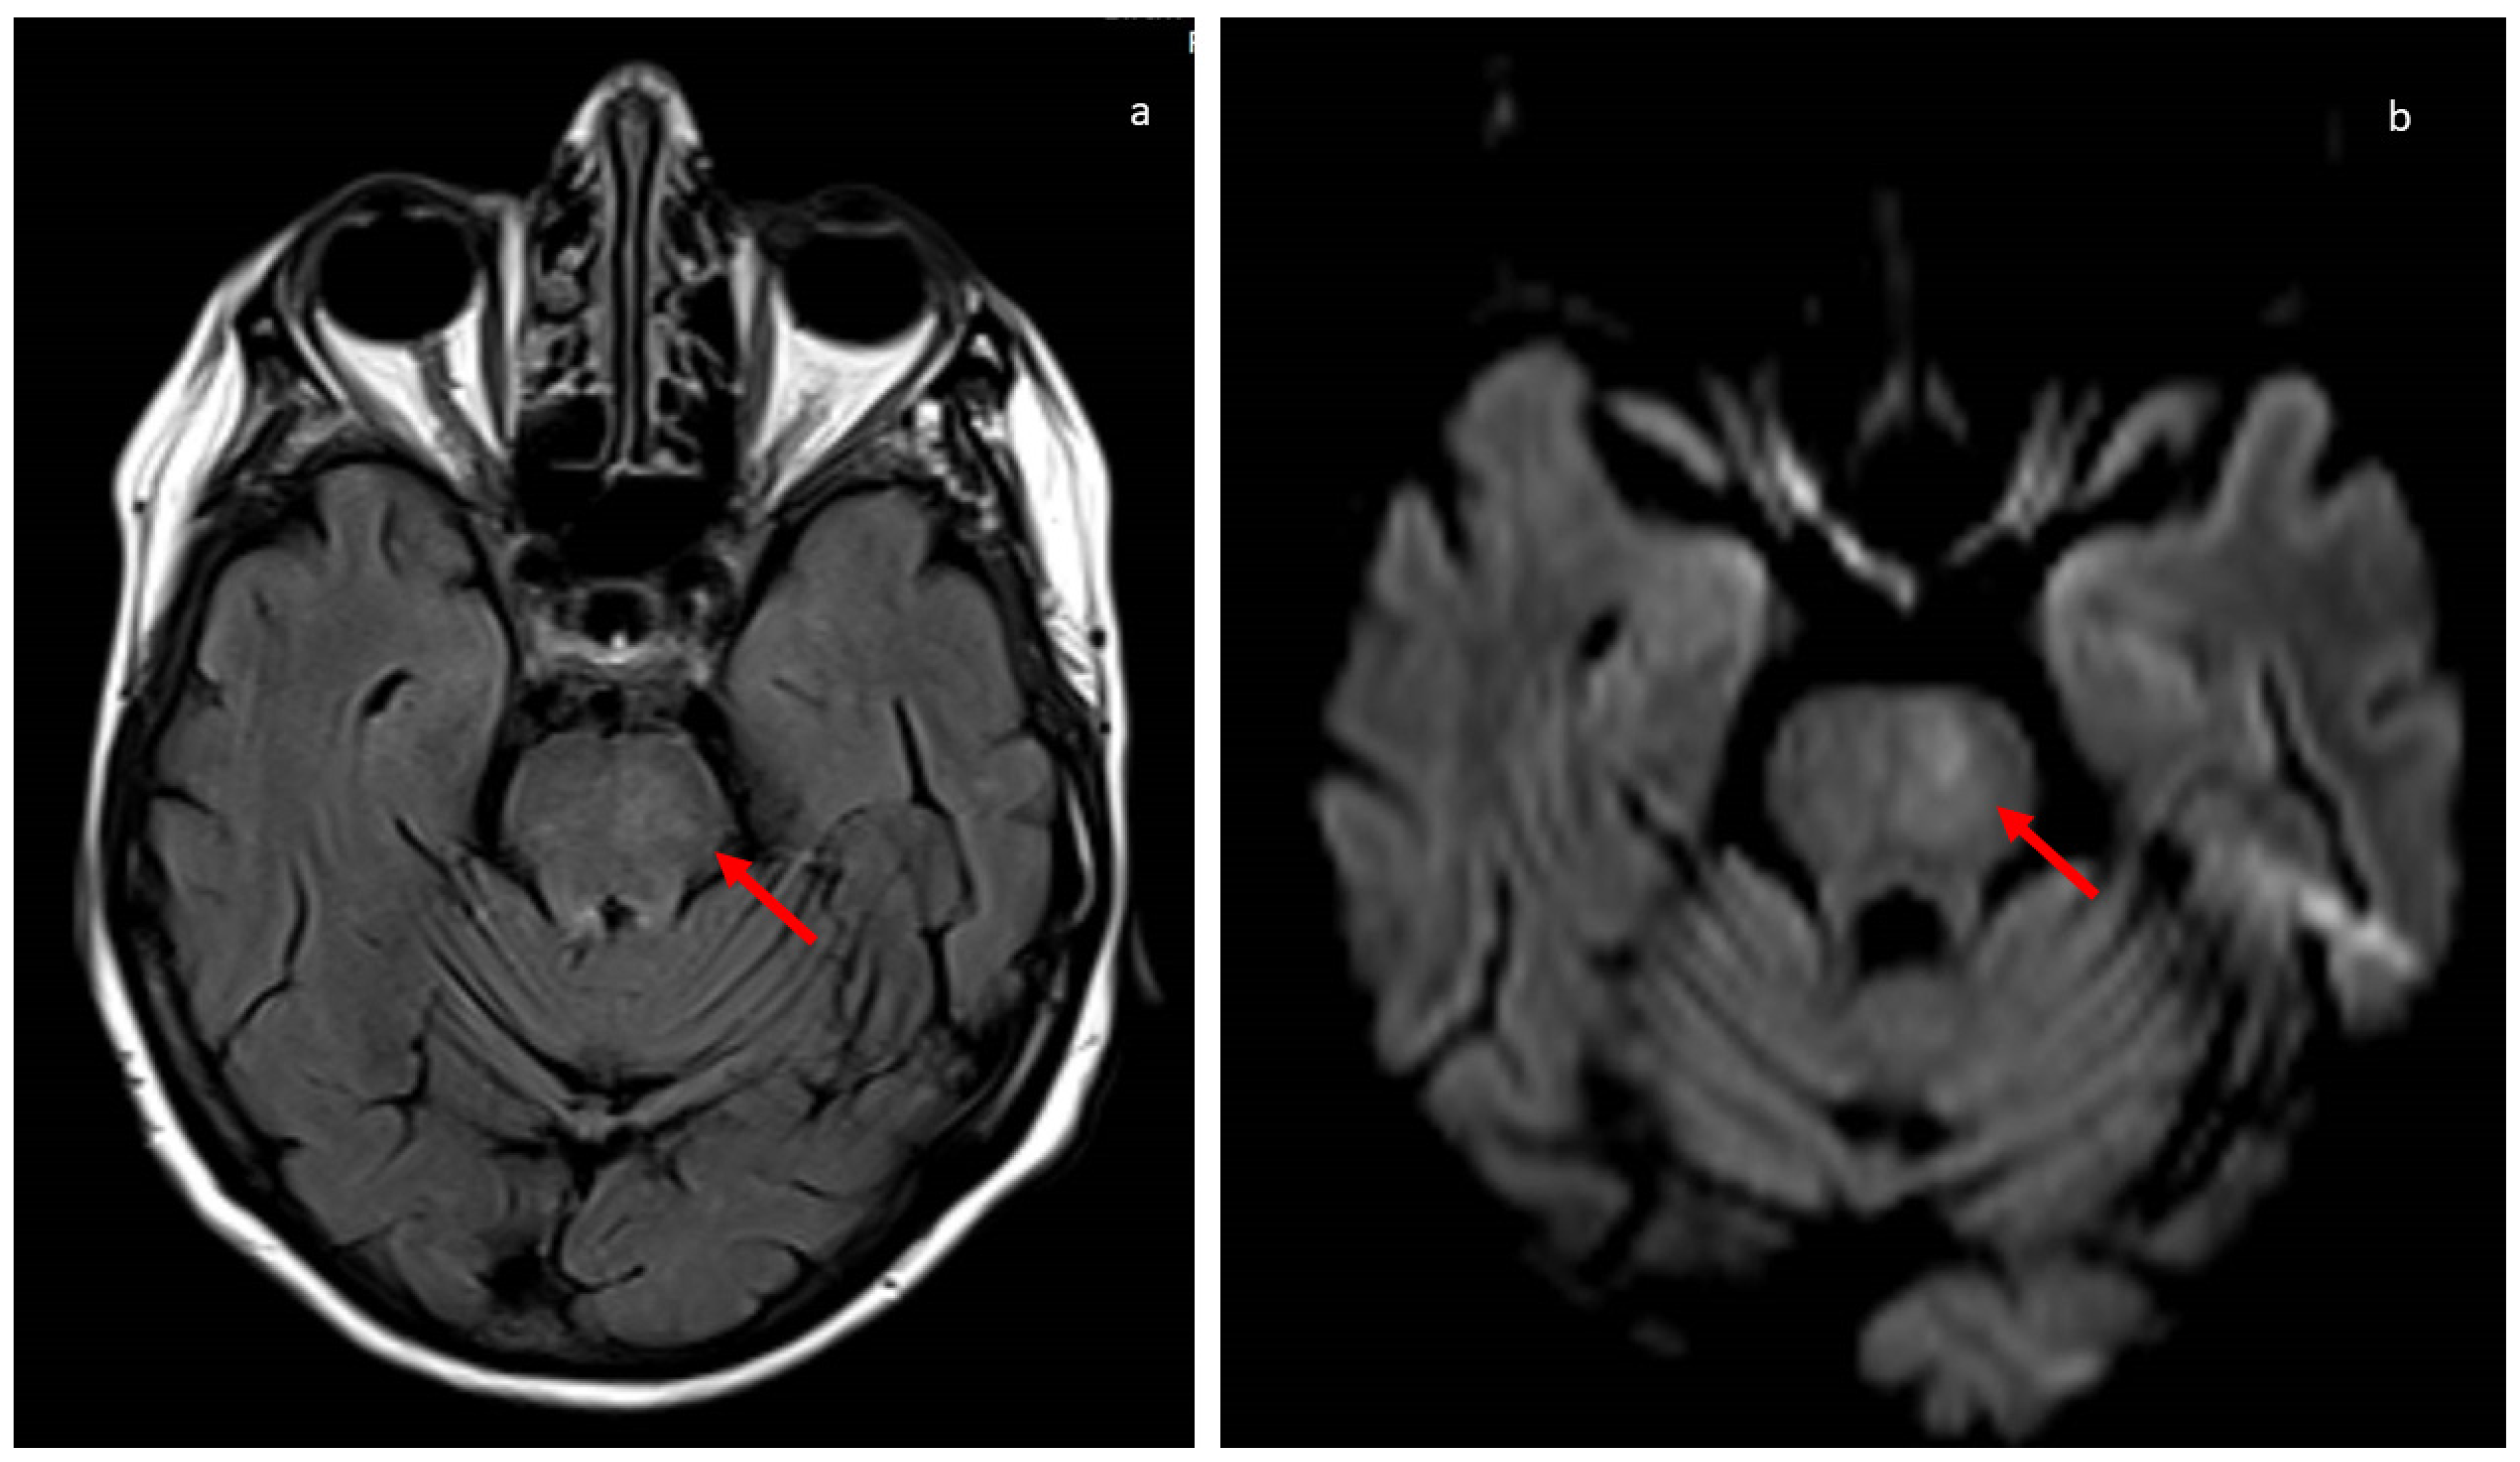

2. Case History

3. Discussion